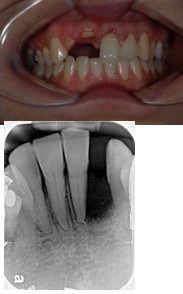

cantilever

This type of bridge has a retainer (or retainers) at one side of the pontic only